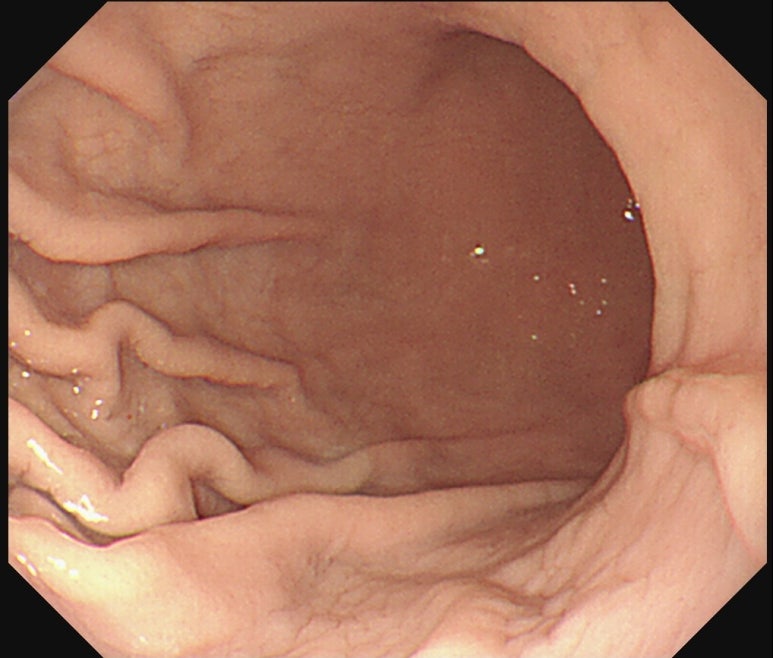

위 점막이 전반적으로 창백하게 보이는

전형적인 빈혈성 위점막 소견이 관찰되었습니다.

**아래는 실제 위내시경에서 관찰된 창백한 위 점막 사진입니다.**

정상적인 위 점막은 연한 분홍색을 띠며

혈관이 적절히 비쳐야 하지만,

중등도 이상의 빈혈에서는

점막이 창백하고 혈관 비침이 감소하거나

사라지는 양상을 보입니다.

이러한 소견은 위장관 출혈이 동반되지 않아도,

전신적 빈혈 상태를 반영하는

중요한 간접 지표가 됩니다.